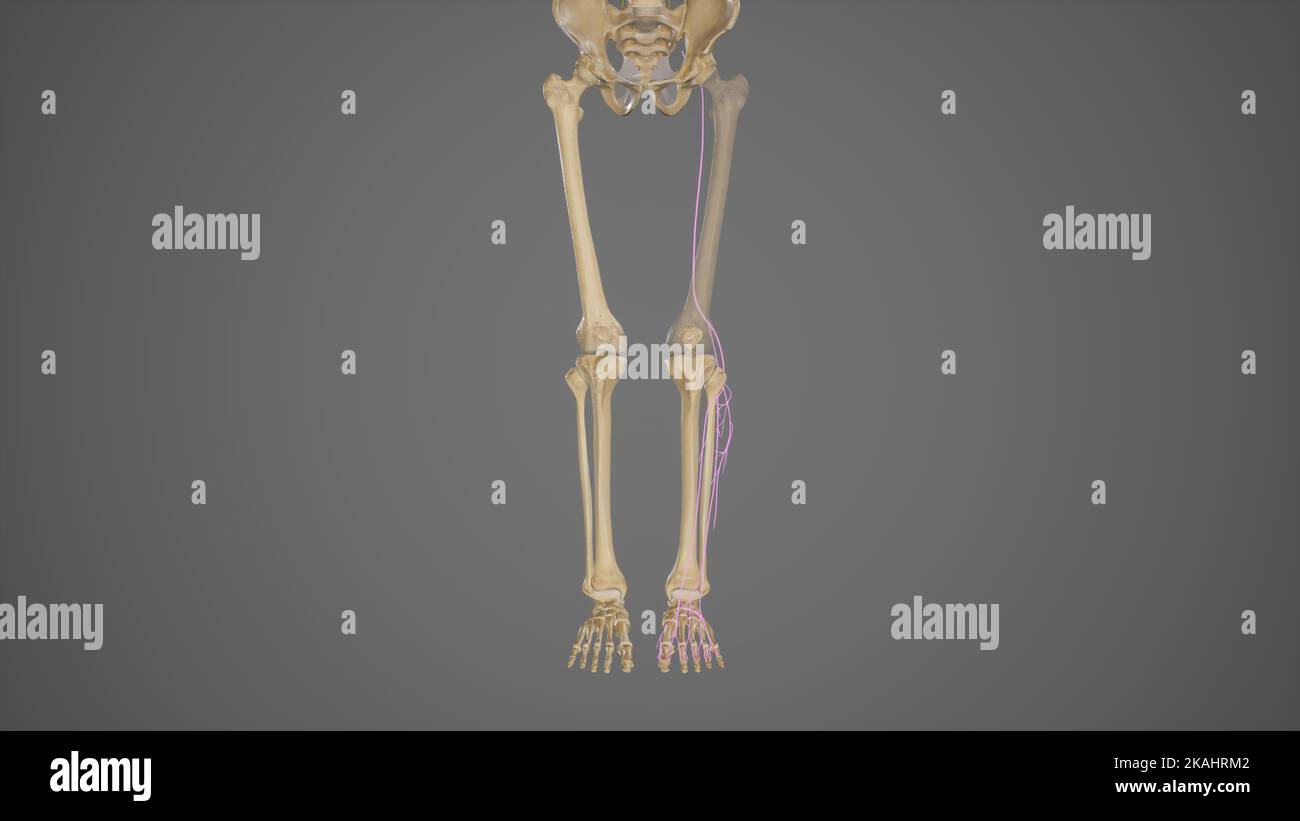

3D rendu médicalement précis illustration nerf fibrlaire commun Banque D'Imageshttps://www.alamyimages.fr/image-license-details/?v=1https://www.alamyimages.fr/3d-rendu-medicalement-precis-illustration-nerf-fibrlaire-commun-image488428642.html

3D rendu médicalement précis illustration nerf fibrlaire commun Banque D'Imageshttps://www.alamyimages.fr/image-license-details/?v=1https://www.alamyimages.fr/3d-rendu-medicalement-precis-illustration-nerf-fibrlaire-commun-image488428642.htmlRF2KAHRM2–3D rendu médicalement précis illustration nerf fibrlaire commun